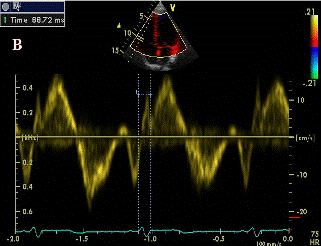

Внутрижелудочковый диссинхронизм оценивался с помощью импульсно-волнового режима тканевого допплера миокарда (ТДМ) и М-режима ЭхоКГ. Из верхушечного доступа в позиции 2 и 4 камер в импульсно-волновом режиме ТДМ измеряли интервал (Q-Ts) от зубца Q ЭКГ до начала систолического (S) допплеровского артефакта (рис.1А) в 6 базальных и 6 медиальных сегментах ЛЖ с учетом его деления на 16 сегментов, предложенного Американским обществом эхокардиографии [16]. Значимой внутрижелудочковой механической задержкой (ВЖМЗ) считали разницу между самыми поздними и самыми ранними участками сокращения ЛЖ более 30 мс [17]. Этим же методом определяли стандартное отклонение (SD) периода от зубца Q на ЭКГ до начала систолического допплеровского артефакта (SD Q-Ts) по 12 временным интервалам. Значимой считали величину более 20,4 мс [18]. Из парастернального доступа в позиции по короткой оси на уровне папиллярных мышц, с помощью М-режима ЭхоКГ измеряли время от максимального систолического движения межжелудочковой перегородки до максимального движения задней стенки ЛЖ. Значимой считали задержку движения задней стенки ЛЖ более 60 мс.

Рис. 1А Схема измерения интервал Q-Ts в сегментах левого желудочка